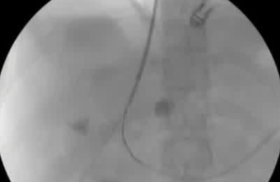

该程序包含以下步骤: 经脾脏入路:在超声引导下,刺穿脾静脉内的一个实质内分支。 在通过脾静脉造影确认了静脉通路后,导管和导丝被推进,以穿过脾静脉并抵达血栓化的门静脉。在门静脉/右门静脉分支处放置圈套器,为TIPS穿刺精准定位。TIPS穿刺圈套器,并穿过圈套器完成TIPS

步骤: 鉴于慢性血栓形成的复杂性: 一种经脾脏途径的门静脉再通术(PVR)。 随后是经颈静脉肝内门体分流术 。

结果:术后影像学检查显示门静脉和脾静脉的血流情况有所改善,且残留血栓极少。